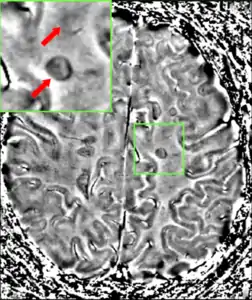

- Lesions – A classic method in which a brain-region of interest is naturally or intentionally destroyed to observe any resulting changes such as degraded or enhanced performance on some behavioral measure. Lesions can be placed with relatively high accuracy "Thanks to a variety of brain 'atlases' which provide a map of brain regions in 3-dimensional "stereotactic coordinates.

The part of the picture emphasized shows the lesion in the brain. This type of lesion can be removed through surgery.- Surgical lesions – Neural tissue is destroyed by removing it surgically.